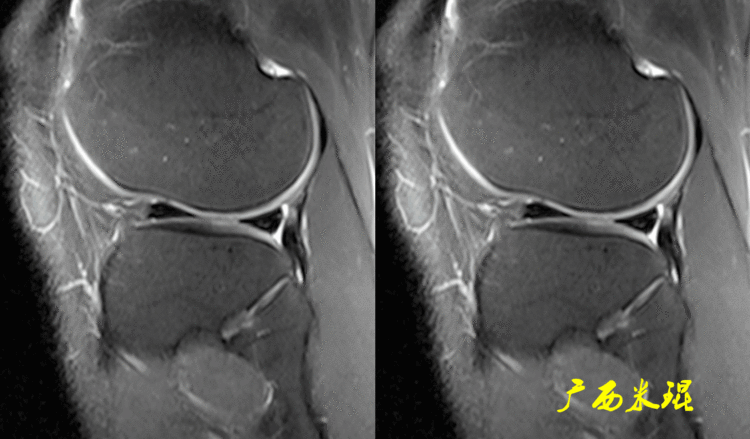

(2)隐窝隐窝是半月板后角与关节囊之间的正常凹陷,与体位等有关,可有可无,一般情况下积液越多隐窝越大,有上下之分,下面这张MR矢状位片见到的是上隐窝,紧贴半月板、光滑、不连通是其特点,也是鉴别要点。

下面这张MR矢状位片见到的是下隐窝,也紧贴半月板、光滑、不连通。

隐窝需要与半月板囊肿鉴别,下面这张MR矢状位片见到的是内侧半月板后角损伤并囊肿形成,与隐窝是有明显区别的。

隐窝还需要与半月板关节囊分离鉴别,下面这张MR矢状位片见到的内侧半月板后角与关节囊完全分离,周围水肿,胫骨内侧平台后方骨水肿;而隐窝是不会连通的。